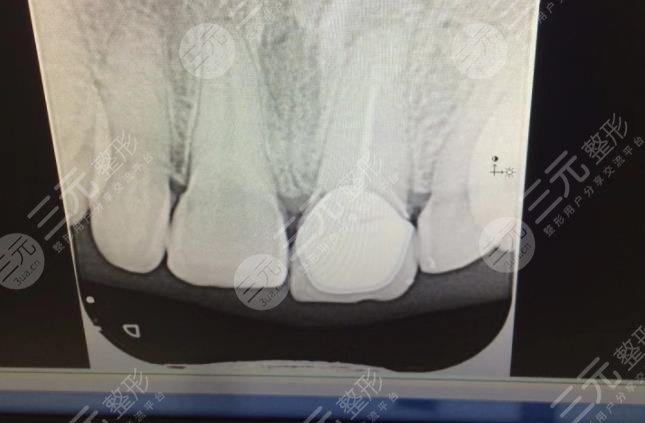

三、佛山爱顿口腔医院种植牙经历分享

于自己的牙齿一定要保护好,牙齿咬住之后就没有办法再长出来了,年纪轻轻的如果就出现了牙齿脱落较为的尴尬,戴假牙不方便,只能做牙齿种植。像我就是一个典型的案例,之前一次意外事故导致了门牙的脱落,像我这种较为注意形象的女生来讲,出现门牙的脱落可以是灾难性的损坏。赶紧到医院咨询了一下,还好医生说现在可以做牙齿种植。

在整个手术的过程当中采用的是局麻。意识较为的清楚,能够感觉到医生的操作,但是却没有觉得疼。手术的速度还是比较快的。牙齿种植的过程其实是比较复杂的,虽然说具体的流程不知道,但是整个持续了半年左右的时间才基本完成牙齿种植。

至于牙齿种植之后的果,确实可以推荐,在做牙齿种植之后,新植入的牙齿较为的坚固,丝毫不逊色于自己的牙。除了坚固之外,关键还是美观。这才是较重要的,通过牙齿种植让我又像原来一样了。